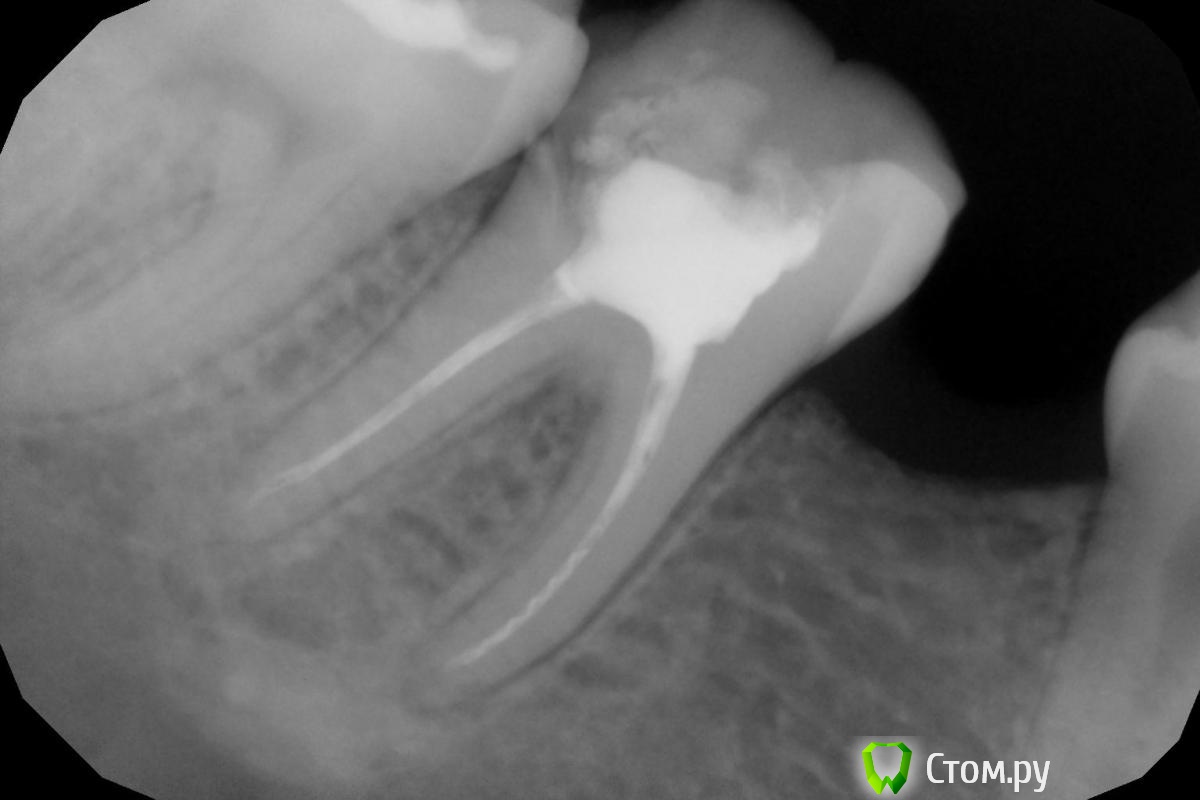

Dr.Sham Опубликовано 25 сентября, 2014 Поделиться Опубликовано 25 сентября, 2014 (изменено) по кругу после препа под коронку хочется видеть около 2 мм тканей зуба. если они есть, значит непрямая реставрация будет прогнозируемо долго стоять при прочих равных. в такой ситуации композитного билдапа достаточно. если этих тканей нет, то чем их меньше, тем компромисснее реставрация. Есть еще вариант эндонакладки керамической с перекрытием всей жевательной поверхности. но опять же показания. рентген мало информативен.По снимку нет дистальной и язычной стенок, что с щечной и медиальной, можно ли к ним приклеиться? Изменено 25 сентября, 2014 пользователем Dr.Sham 1 Ссылка на комментарий

faity Опубликовано 25 сентября, 2014 Поделиться Опубликовано 25 сентября, 2014 уберите пломбу целиком, сделайте снимок таком виде рентген и фото, а потом вытащите лентуло из медиального канала.если все удастся- ВКВ и коронку Ссылка на комментарий

DR.P Опубликовано 3 октября, 2014 Поделиться Опубликовано 3 октября, 2014 Высылаю фото, как обещал Ссылка на комментарий

DR.P Опубликовано 6 октября, 2014 Поделиться Опубликовано 6 октября, 2014 Не за что. Снимок до не делал, фотоаппарат не брал в тот день. Постараюсь объяснить на словах: пациент обратился с зубом 1.6 (имеется стенка щечная, все остальное отломано до уровня десны, ткани плотные чистые (некариозные). Терапевт пролечила эндодонтически. Я отпрепарировал предварительно щечную стенку под коронку (уступ на уровне десны), остальное под вкладку, снизил щечную стенку до необходимой высоты (чем ниже - тем толще - 2 мм), распломбировал 3 корневых канала, снял слепок (база жесткая zetaplus), коррегир - speedex. Каналонаполнителем без армирования штифтами.Затем планирую коронку ДЦ 1 Ссылка на комментарий

Nadzivany Опубликовано 12 октября, 2014 Поделиться Опубликовано 12 октября, 2014 Высылаю фото, как обещал Разборные вкладки не стоит делать. Очень большой риск, что вы сделаете скрытую перфорацию в каналах. Тем более при таком диаметре развертки. Ссылка на комментарий